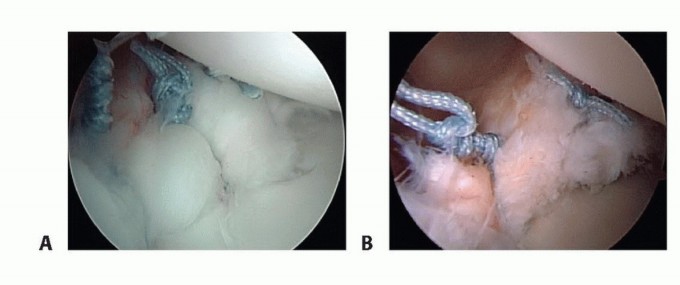

Anchor Placement and Suture Passing

Anchor placement begins at the most inferior aspect of the tear, typically at the 5:30 position for a right shoulder. This foundational anchor is the most critical; it dictates the tension of the inferior glenohumeral ligament and the success of the entire shift. The drill guide is introduced through the anteroinferior portal, ensuring a trajectory that bisects the glenoid face to avoid joint penetration (the "deadman's angle"). We utilize modern biocomposite or all-suture anchors, typically 2.4mm to 3.0mm in diameter, to minimize bone removal while maximizing pull-out strength.

Once the anchor is deployed, suture passing is executed to achieve a distinct inferior-to-superior and medial-to-lateral shift of the capsulolabral tissue. Various passing devices can be utilized, including curved suture lassos or direct penetrating devices. The device is passed through the capsule first, inferior and medial to the anchor, and then through the labrum.

Image

This "pinch" of tissue ensures that when the knot is tied (or the knotless mechanism is tensioned), the capsule is plicated and drawn up onto the articular margin, recreating the essential bumper effect. Subsequent anchors are placed sequentially moving superiorly along the anterior rim, typically at the 4 o'clock and 3 o'clock positions, depending on the extent of the lesion.